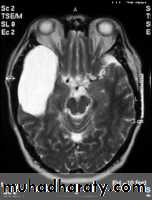

Axial T2-weighted MRI image through the midbrain, showing a right middle cranial fossa homogeneous lesion) with CSF signal intensity and no perceptible wall or internal complexity. There is associated remodeling of the adjacent sphenoid bone and brain displacement..